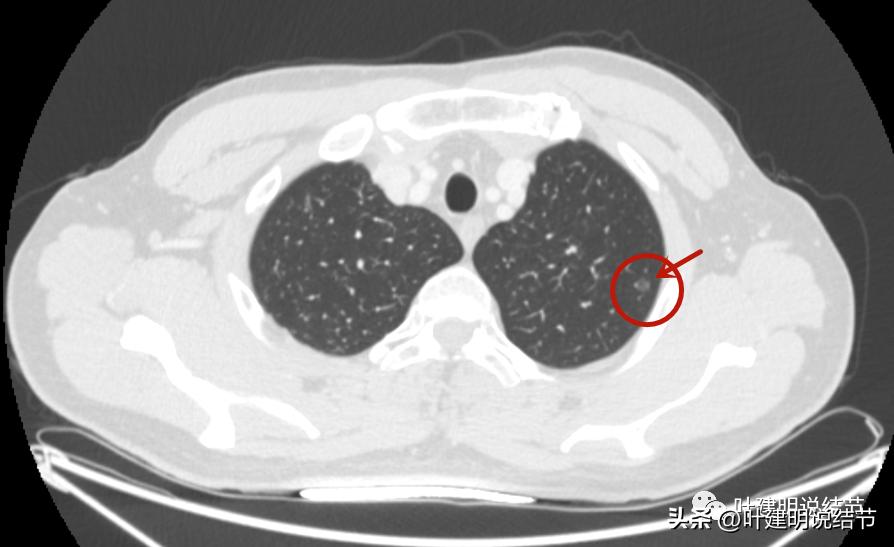

中间密度比周围区域更低一点。

瘤肺边界清。

感觉之所以中间密度偏低,是不是因为病灶边上有血管,从而血管围成类近一圈,而肿瘤的真实部分密度是非常低的,看上去显得低密度空泡征似的?

周围不同方向也有血管。